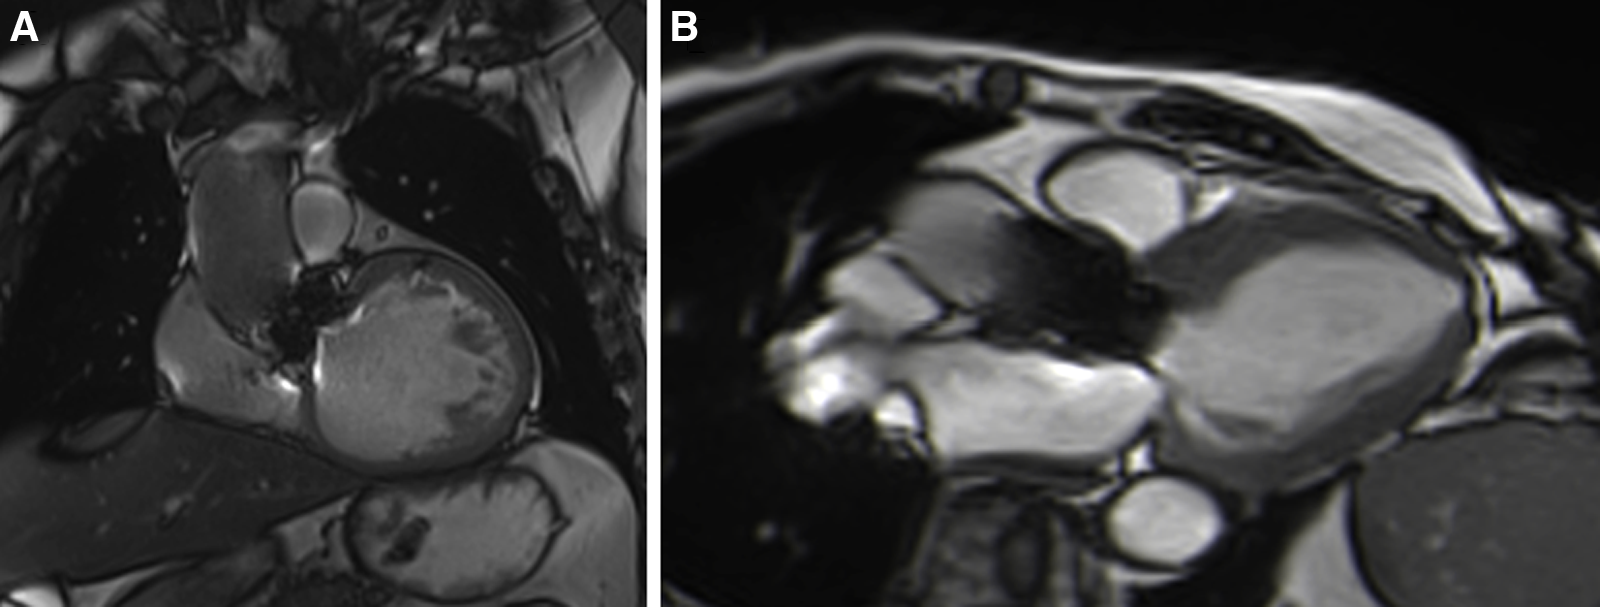

Patients with either SAVR or TAVI can safely have CMR at 1.5 or 3 T (15). However, magnetic field inhomogeneities related to the metal component of the prosthesis generates artefacts (localized signal voids), especially with stented bioprosthetic aortic valves [made from porcine aortic valves or from bovine pericardial tissue mounted on a flexible plastic or titanium model frame (stent)] and TAVI (metallic frame with a valve mounted in the centre) (Figure 1). These artefacts often limit accurate assessment of valve planimetry and Valsalva measurements, making it impossible to identify the origin of aortic regurgitation. In contrast, stentless bioprosthetic aortic valves are made from porcine aortic roots or cryopreserved human cadaveric aortic roots with no metallic components. Thus, their appearance is consequently very similar to that of native aortic valves, without any artefacts (Figure 2), as well as that of homografts and autografts (human tissue valves). However, all the CMR acquisitions described in Table 1 remain highly challenging in clinical practice for arrhythmic patients and those who have difficulty holding their breath. These two conditions can cause motion artefacts which can blur or distort images.

Figure 1

Example of a surgical stented bioprosthetic aortic valve (perimount) visualized in the coronal left ventricular outflow tract (LVOT) (A) and the medtronic corevalve prosthesis visualized in a three-chamber view (B). The ferromagnetic component of the prostheses generated important artefacts, particularly for the corevalve prosthesis.

Figure 2

Example of a stentless aortic prosthesis (freestyle) visualized in three-chamber view bSSFP sequences, free from any artefacts and appearing as a native aortic valve.